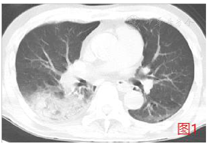

心电图检查示室上性心动过速,ST-T改变,性质待定;胸部CT(图1)示双肺纹理紊乱,双肺可见多发囊状透亮影,以双肺上叶为著,双下肺可见多发条片状密度增高影,右肺下叶可见实变影,双侧胸膜增厚。